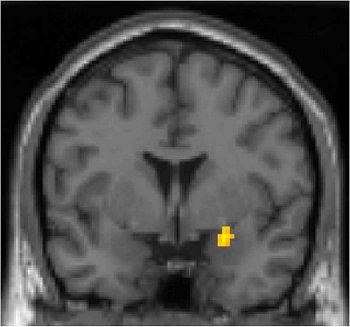

![]() |

| Two-dimensional (above) and 3D (below) MR images of the region of amygdala that is more active for both African Americans and Caucasian Americans when looking at African-American photos, as compared to Caucasian-American photos. Images courtesy of the Social Cognitive Neuroscience Laboratory and Matthew Lieberman, Ph.D. |

In the whole-brain analysis, white participants produced greater amygdala activity to black targets than to white ones. Additionally, the ventromedial prefrontal cortex, the hippocampus, and the midbrain in the area of the substantia nigra were more active in response to black faces than white faces.

But in an interesting twist, the researchers found that both groups produced a greater response in the right amygdala to black targets than to white ones. During perceptual encoding, African-American participants produced greater amygdala activity to black targets than white ones.